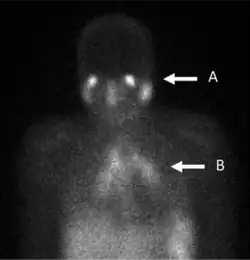

In the past, the gallium scan was the gold standard for lymphoma staging, until it was replaced by positron emission tomography (PET) using 18F-fluorodeoxyglucose (FDG).[7][8] 67Ga-citrate imaging is still used to image inflammation and chronic infections, and it still sometimes locates unsuspected tumors as it is taken up by many kinds of cancer cells in amounts that exceed those of normal tissues. Thus, an increased uptake of gallium-67 may indicate a new or old infection, an inflammatory focus from any cause, or a cancerous tumor.

- Evaluation and follow-up of active lymphocytic or granulomatous inflammatory processes such as sarcoidosis or tuberculosis.[20]